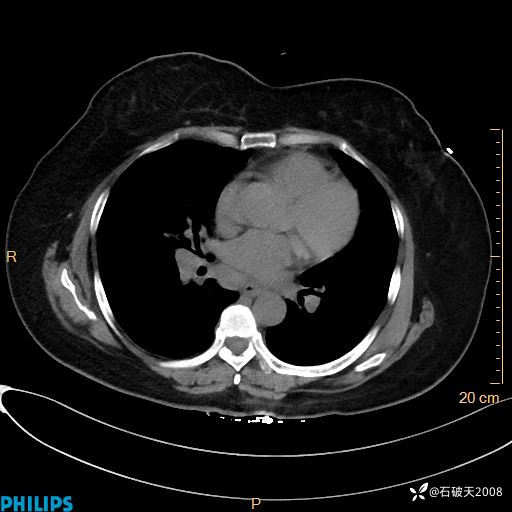

动脉期